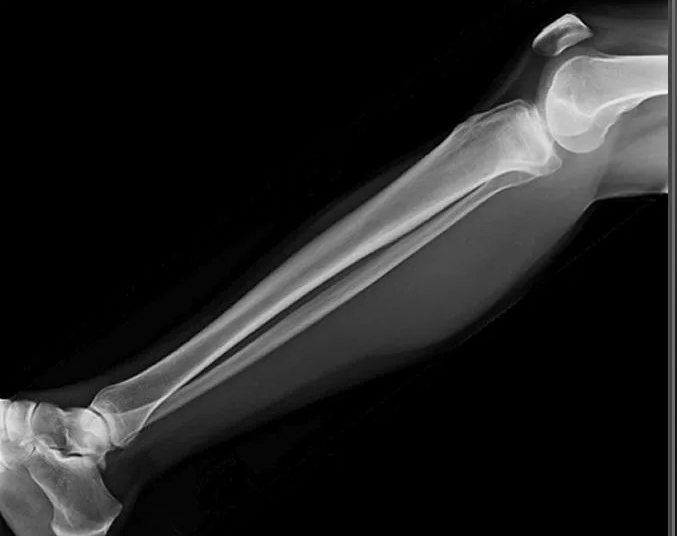

Большая берцовая кость ― вторая по толщине после бедренной ― вместе с малоберцовой образует часть нижней конечности ― голень. Она принимает на себя вес человека, позволяя ему свободно передвигаться и поднимать значительные грузы. Для повреждения голеней требуется значительная сила, какая встречается, например, при ДТП. С другой стороны, хронические патологии обеих костей, а также прилегающих к ним суставов, медленно и незаметно наносят не меньший вред, лишая мобильности.

При первых признаках заболеваний или травмы лучше проконсультироваться со специалистом и приступить к лечению на ранней стадии. Ортопед, травматолог или онколог направляют на рентген обеих голеней, если необходимо сравнить состояние симметричных участков, при травме или хронической патологии и при подозрении на аномалии развития. Выбор данного вида диагностики вызван простотой и доступностью методики, ее безболезненностью для пациента и высокой информативностью для врача.

Что покажет рентген костей голени обеих ног

• Изменения в мягких тканях: инородные тела, осколки, отеки;

• Патологии суставов, вошедших в снимок: вывихи и воспалительные процессы;

• Переломы костей: их расположение, уровень заживления и степень консолидации, соответствие сроку травмы;

• Состояние костной ткани: подозрение на онкологические изменения, остеопороз, остеосклероз, остеонекроз;

• Состояние надкостницы: истончение или утолщение.